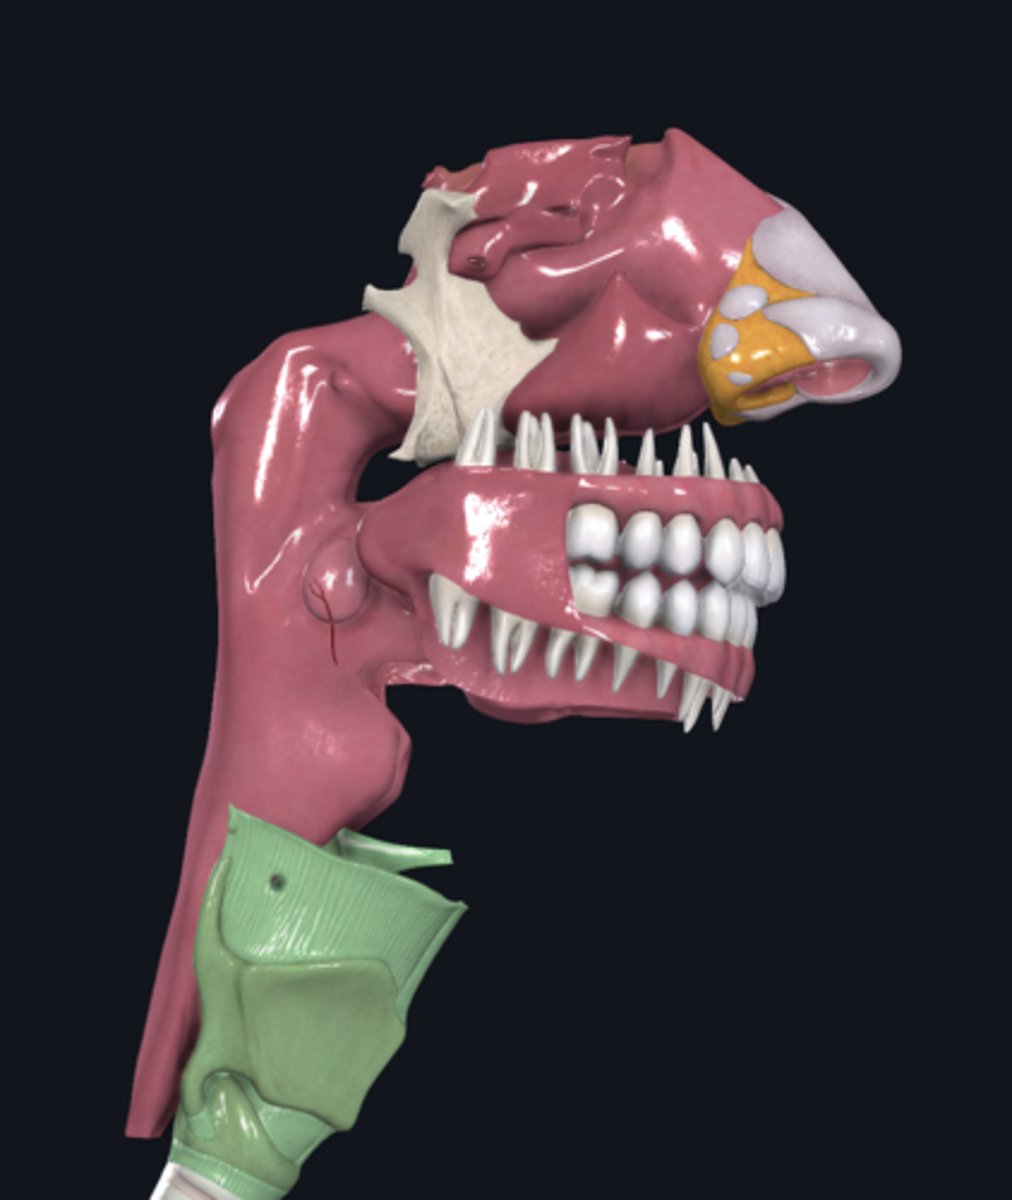

larynx

name the green portion

hyoid bone

name the green portion

thyroid cartilage

name the green portion

cricoid cartilage

name the green portion

arytenoid cartilage

name this cartilage